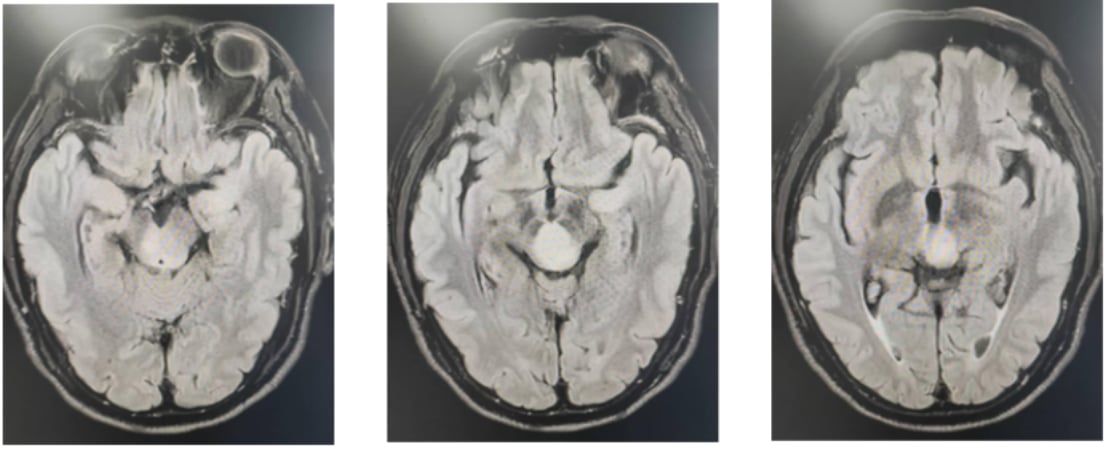

本案例的主人公是一位61岁的男性患者,因出现“左眼视物模糊、左眼睑下垂及左眼球固定”等症状长达两个月而就医。初步的MR检查显示,其中脑、丘脑等多个部位存在异常信号,初步考虑为低级别胶质瘤。为了进一步明确诊断,患者接受了PET/MR检查和立体定向中脑病变活检术。最终,术后病理结果结合免疫组化分析,明确诊断为:弥漫性中线胶质瘤(DMG),H3K27M突变型,WHO 4级。

图1 初诊影像学